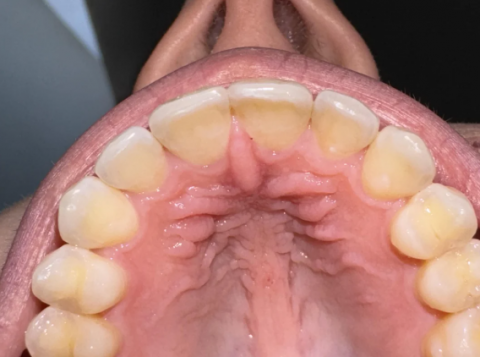

Intraoral Examination: Palatal Rugae, Teeth Discoloration, and Enamel Wear

| Feature | Observation | Dental Terminology / Analysis |

| Palate Texture | The central area of the palate shows prominent, irregular, firm ridges running side-to-side behind the front teeth. | This is the Palatal Rugae (or transverse palatine folds). This texture is completely normal and is a standard feature of the human oral anatomy. |

| Palate Color | Pink and moist, appearing healthy. | Healthy mucosal tissue. No signs of inflammation, lesions, or major irritation are visible. |

| Teeth Color | Generally yellowish-white. The chewing/biting edges (incisal edges) are whiter/more translucent than the body (cervical third) of the teeth. | Normal color variation. The yellowing is likely due to the underlying dentin (which is naturally yellow) showing through the thin enamel. This can be treated with professional teeth whitening. |

| Teeth Shape/Wear | Some minor wear or flattening is visible on the incisal (biting) edges of the front teeth. | Suggests slight enamel wear or abrasion. This should be monitored by a dentist, possibly related to bite issues or habits like bruxism (teeth grinding). |

| Gums | Pink and appear firm and healthy around the necks of the teeth. | Healthy gingiva. No signs of gingivitis (inflammation) or periodontitis are evident. |

Client Concern: "Is this texture on my palate normal? Why does it look like that?"

Answer: Yes, this texture is completely normal!

The ridges are called the Palatal Rugae ("wrinkles" or "folds").

Why it looks like that: The rugae are permanent, irregularly shaped connective tissue ridges covered by the mucous membrane on the front part of the hard palate. Their function includes aiding the tongue in forming a bolus (mass of food) during chewing and helping with speech. Like fingerprints, the pattern of palatal rugae is unique to every individual.

Primary Condition: Visually healthy oral anatomy (palate and gums).

Secondary Findings: Dental discoloration and minor evidence of enamel wear/abrasion.